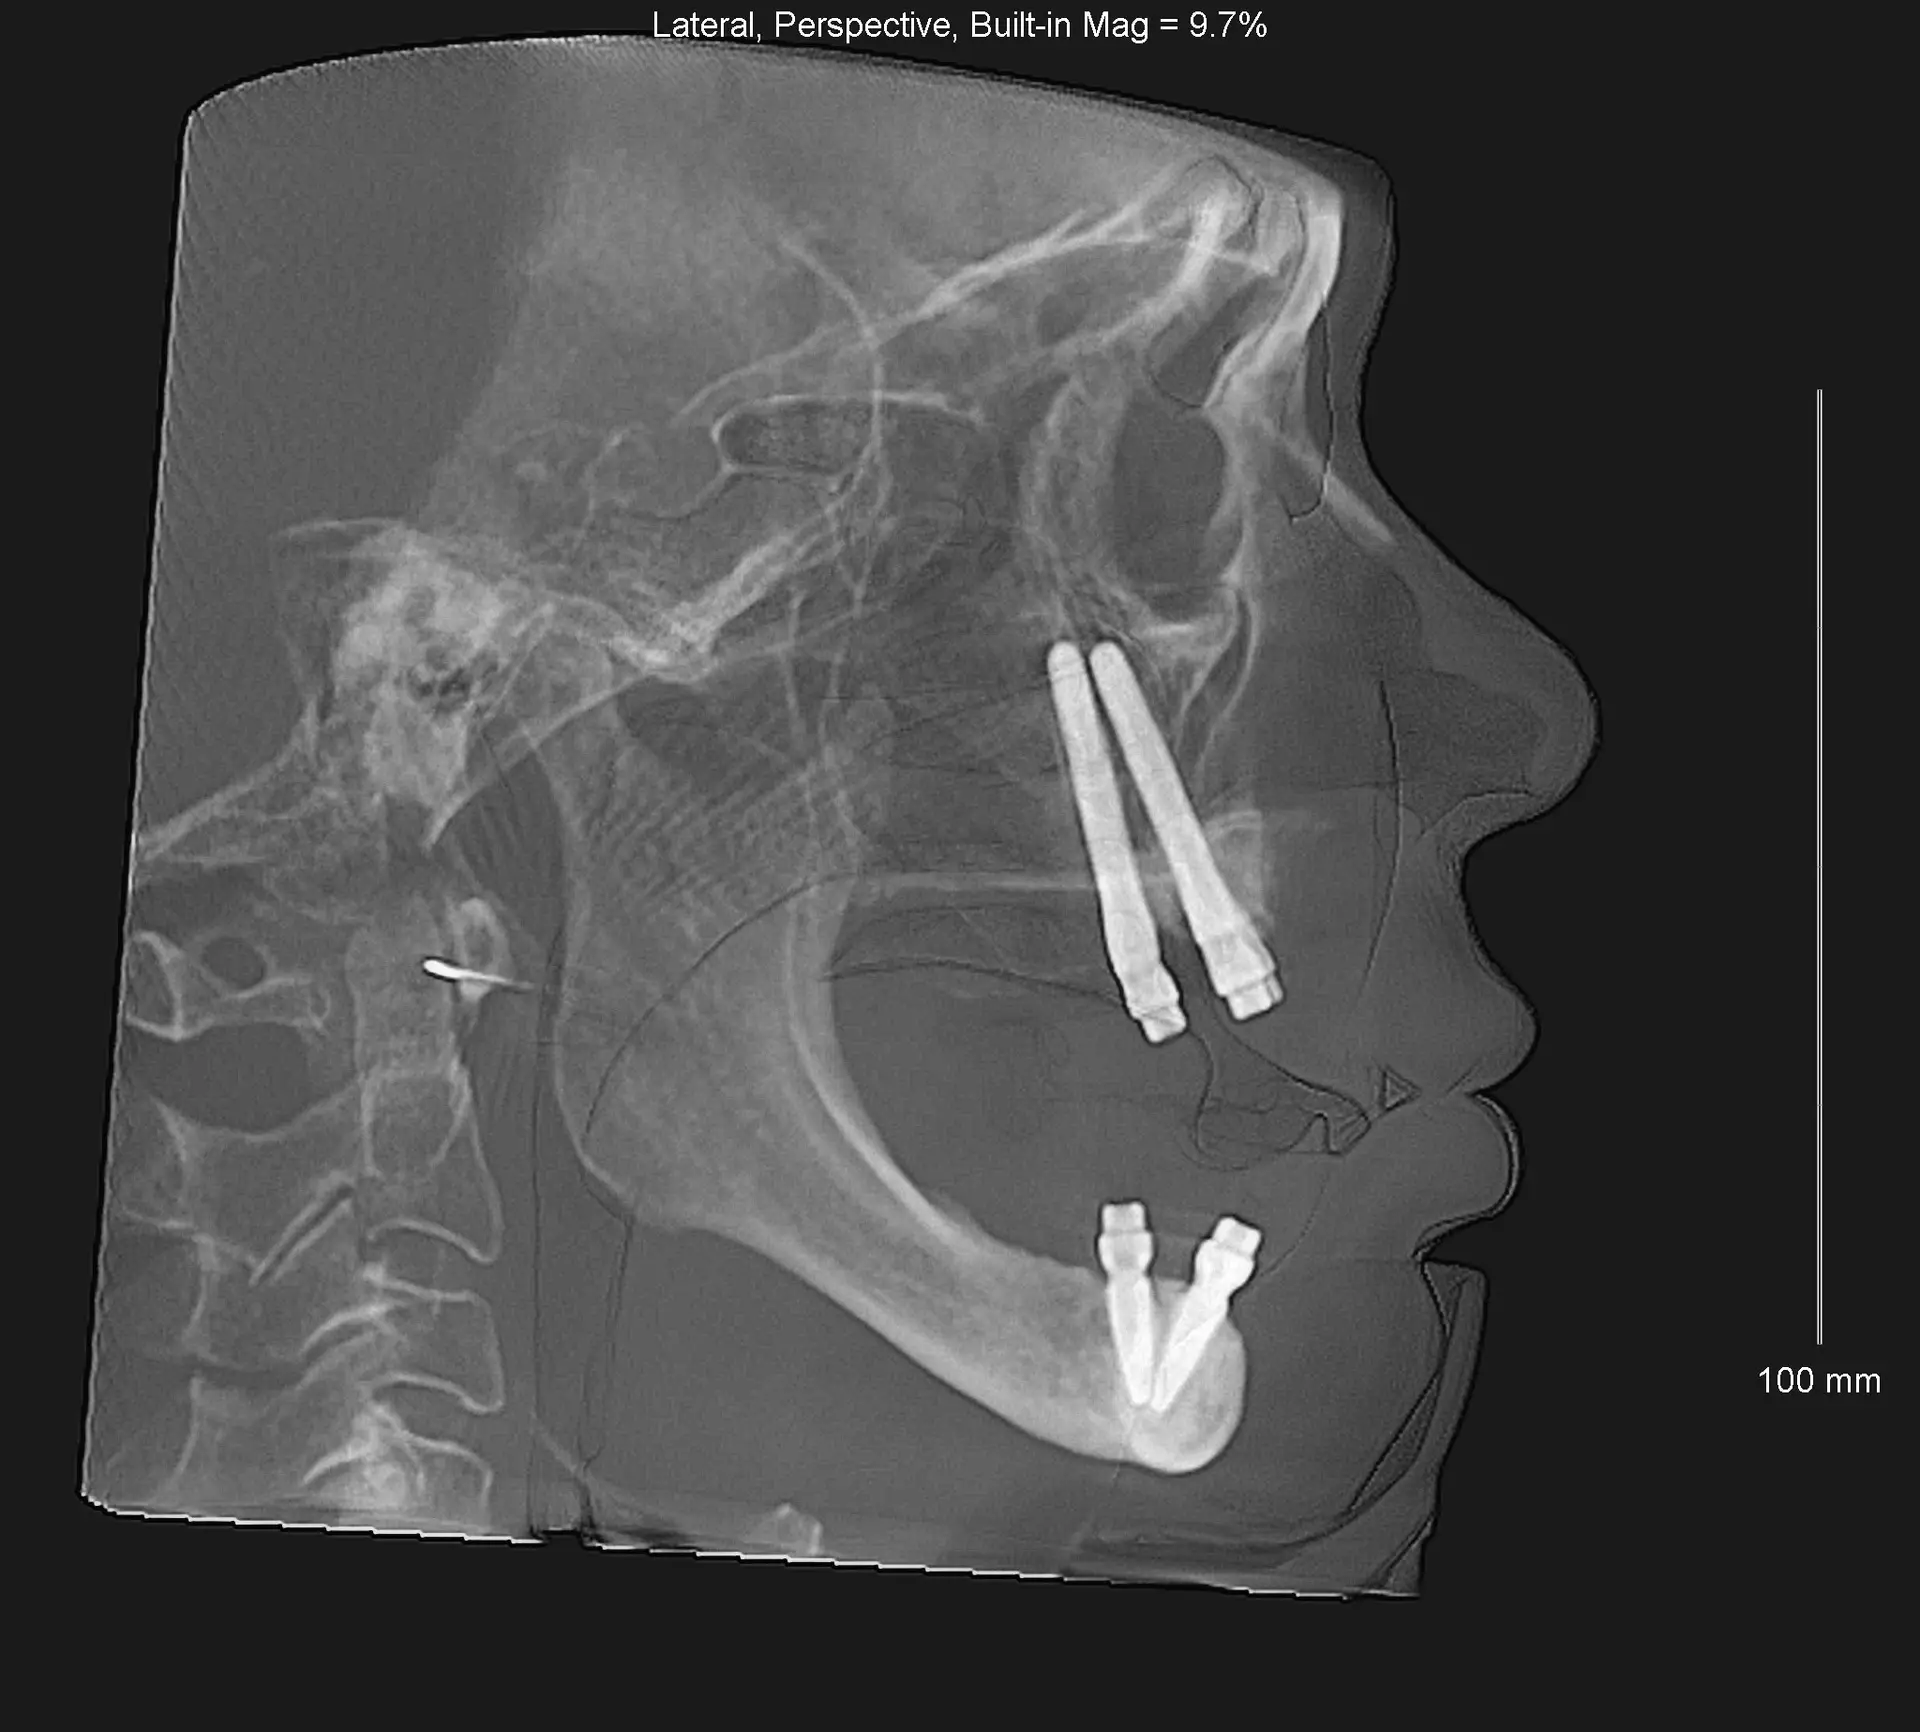

Clinical Case Example

Documented case of Ana, a patient presenting with severe bone loss and failed implants. She was treated by our faculty member, Dr. Jay Neugarten, during the ZAGA Course as part of a live surgical demonstration for course participants. Treatment involved quad zygomatic implants and one pterygoid implant to improve stability. Using the ZAGA Approach, we were able to successfully rehabilitate the case despite the previous implant failures and deliver an immediate prosthesis on the same day as surgery. This case represents part of the clinical education and knowledge participants gain during the ZAGA course.